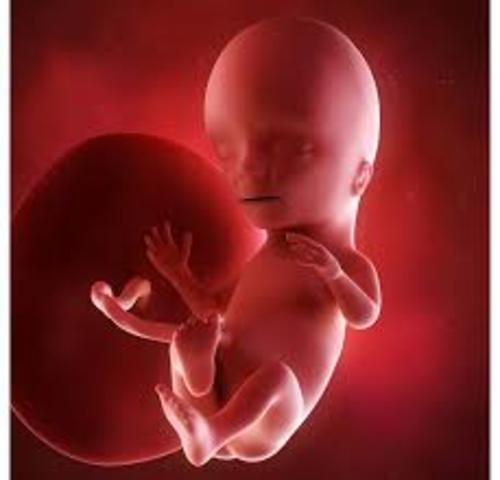

Cerca de esta semana 11 del embarazo, el feto empieza a generar sus propios glóbulos rojos. Además, comenzará a producir orina, el principal componente del líquido amniótico. La piel es todavía transparente y su cuerpo se va alargando. Aun así, la cabeza es un tercio del largo del cuerpo. En el caso de tener un hijo varón, esta semana sus testículos comenzarán a producir la hormona masculina testosterona. Ya medirá casi 4-5 centímetros y pesará hasta 8 gramos.

ras 12 semanas de embarazo, todos los sistemas principales del cuerpo y órganos como el estómago, el hígado, los pulmones, el páncreas y los intestinos están formados y en su sitio, aunque no están desarrollados del todo. La cabeza llega a ser más redondeada y su perfil se va definiendo. Además, empezarás a escuchar el latido del corazón del bebé con más facilidad. Todavía mide 6 centímetros y tiene unos 14 gramos de peso.

A las 13 semanas de embarazo, el bebé está comenzando un período en el que aumentará rápidamente de peso y longitud. Ahora tiene aproximadamente entre 6.5 y 7.5 cm de largo y pesa entre 14 y 21 gramos. Durante esta semana de embarazo las orejas y los ojos se están moviendo hacia su posición. Ya han aparecido los 27 huesos de la mano y pronto el bebé comenzará a chuparse el dedo. Es un momento muy especial, ya lo verás.

Con 14 semanas de embarazo el bebé ya tendrá las orejas en su lugar definitivo aunque seguirán creciendo a lo largo de las semanas siguientes. Puede que haga sus primeros movimientos con la cabeza. Podrá moverla de un lado a otro. No será hasta la semana siguiente cuando aparezcan los primeros movimientos similares a los de una actividad respiratoria: dilataciones y contracciones de la caja torácica.

Alrededor de la semana 15 de embarazo la piel del bebé se recubre de un vello suave y delgado llamado lanugo, el cual desaparecerá casi por completo antes del nacimiento. En esta etapa algunos bebés se chupan el dedo. El niño sigue creciendo. Mide unos 11 centímetros y ya pesa alrededor de 50 gramos. El cuello se alarga y la cabeza no está tan doblada hacia el pecho.